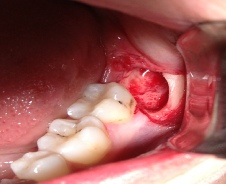

ΑΚΡΟΡΡΙΖΕΚΤΟΜΗ ΚΑΙ ΑΝΑΣΤΡΟΦΗ ΕΜΦΡΑΞΗ ΣΕ ΑΠΟΝΕΥΡΩΜΕΝA  ΔΟΝΤΙA ΚΑΙ ΑΦΑΙΡΕΣΗ ΚΥΣΤΕΩΝ